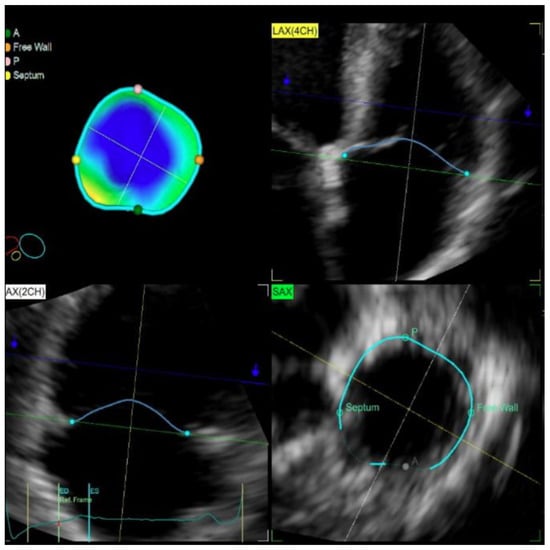

The digitally stored live 3D zoom dataset was imported into the 4D Auto TVQ quantification (GE Healthcare, Horten, Norway) workstation to analyze the TV geometry (Figure 1). Anterior–posterior and septal–lateral diameters of the TV, as well as major and minor axis diameter, the TV annular area, perimeter, and sphericity index, were obtained on a mid-systolic and mid-diastolic frame. The closed leaflets were traced in mid-systole on successive equidistant long-axis planes to obtain the leaflet tethering height and 3D tenting volume.

Figure 1. Three-dimensional TV echocardiographic measurements.